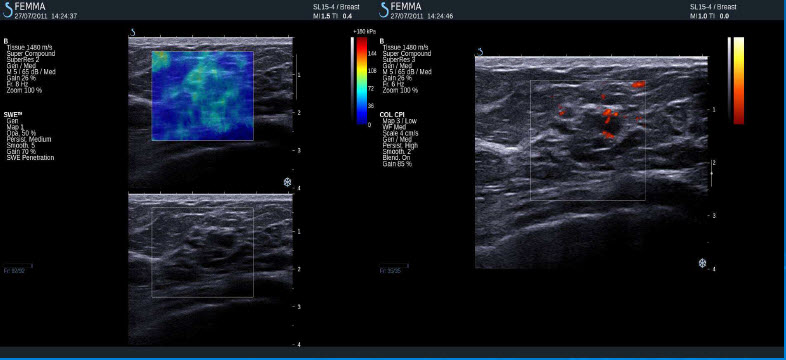

Normální tkáň prsu

Cysty

Fibroadenom

Maligní tumor (IDC)